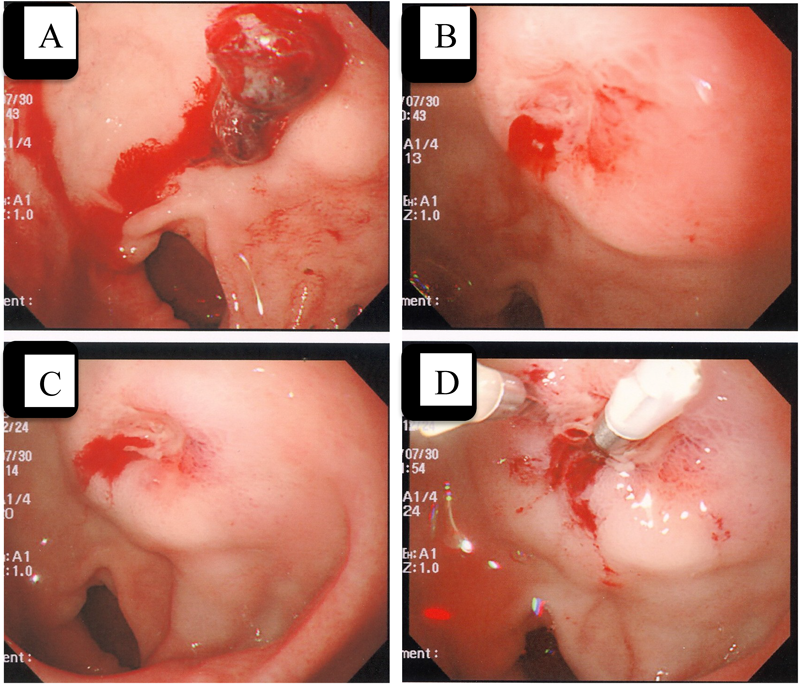

Fig. 2 A case of a duodenal ulcer treated successfully with endoscopic clipping

A: Adherent blood clot. B: Spurting bleed from the exposed vessel. C: Local injection of hypertonic saline_epinephrine. D: Clipping of the responsible vessel.

消化管出血を3名の患者で計6回経験した.腹痛を訴えたのは1例のみで2人は腹痛を訴えなかった.5回は緊急輸血が必要となり,全例ワーファリン,アスピリン内服中であった.症例1–①~④は同一症例(無脾症)であり,1–①,②の時点での上下部消化管造影,メッケルシンチと数日後に行った内視鏡では出血部位の診断がつかなかった.1–③のときに尿中ピロリ菌抗原陽性が判明,除菌が不成功であったため潰瘍の懸念からアスピリンが中止された.13歳のときにメトロニダゾール併用でピロリ菌除菌が成功し,アスピリン腸溶錠を隔日内服で再開.しかし,15歳で房室弁人工弁置換手術を受け,弁置換術後2ヶ月後に潰瘍を再発した(症例1–④).この際,輸血後の緊急内視鏡で十二指腸球部後壁に凝血塊の付着を認め,その下に約3 mmの浅い潰瘍と動脈性に出血する露出血管を確認,高調食塩水局注でも完全に止血できなかったため,クリッピングにて止血を行った(Fig. 2).症例2は19歳男性(類同交通のあるPA-IVS,陳旧性心筋梗塞,左冠動脈前下降枝閉塞)で,数日前から黒色便に気づいていたが腹痛がないため様子を見ていたところ,顔色不良となりプレショック状態で入院した.症例3の9歳男児(TAIIc, CoA)のみが腹痛を訴え,近医小児科を受診したが腹部エコーで異常なく,便秘と診断され浣腸で様子を見ていたところ,5日後にプレショックとなった.再三,母親に黒色便がないかと注意を促していたにもかかわらず,母親は気づけなかった.症例1–③以外では緊急で輸血が必要であり,ワーファリン,アスピリン中止のうえ,メナテトレノンを使用し,全例プロトンポンプ阻害薬(PPI)併用が開始された.